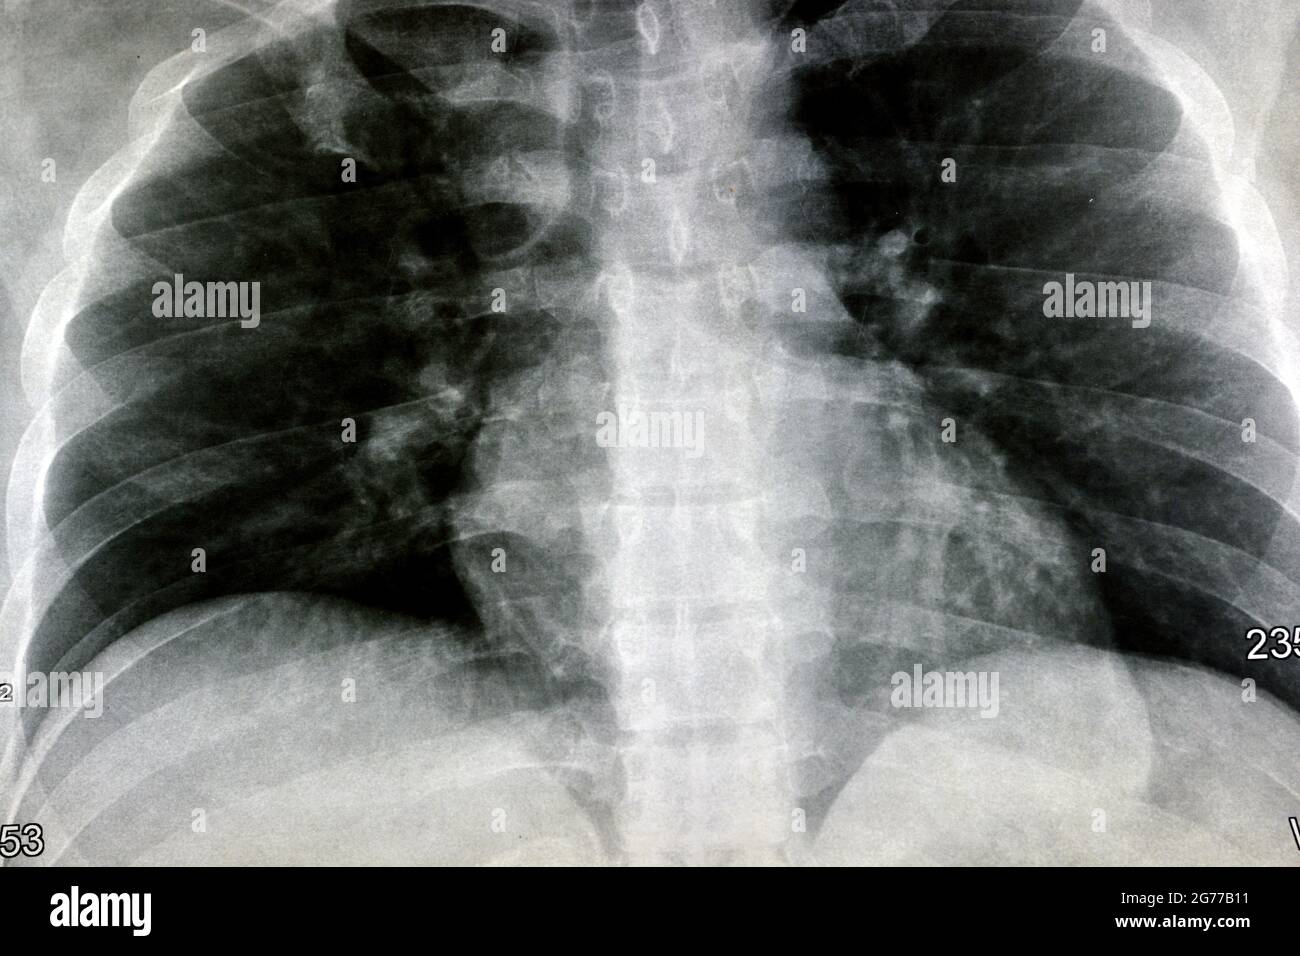

Chest X Ray Bronchitis Vs Normal . Acute bronchitis is a clinical diagnosis of cough due to acute inflammation of the trachea and large airways without pneumonia. Learn how to rule out secondary causes, educate patients, and avoid. The cxr findings may occasionally reveal increased. These differences include areas of hyperinflation, hazy or.

The cxr findings may occasionally reveal increased. Acute bronchitis is a clinical diagnosis of cough due to acute inflammation of the trachea and large airways without pneumonia. Learn how to rule out secondary causes, educate patients, and avoid. These differences include areas of hyperinflation, hazy or.

Chest X Ray Bronchitis Vs Normal Learn how to rule out secondary causes, educate patients, and avoid. The cxr findings may occasionally reveal increased. Acute bronchitis is a clinical diagnosis of cough due to acute inflammation of the trachea and large airways without pneumonia. Learn how to rule out secondary causes, educate patients, and avoid. These differences include areas of hyperinflation, hazy or.